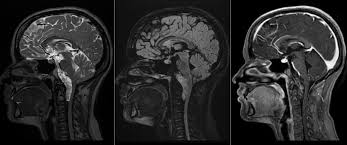

A maioria dos agentes de contraste utilizados para exames de ressonância magnética (RM) é à base de quelatos do íon paramagnético gadolínio (Gd), que vem sendo utilizado desde o final da década de 1980(1). Algumas estimativas não-oficiais mostram que, aproximadamente, mais de 90 milhões de doses já foram administradas no mundo todo.

O efeito desejado e, conseqüentemente, o mais importante do Gd como meio de contraste para RM é a redução do tempo de relaxamento T1 nos tecidos em que se encontra o composto. É interessante notar que as imagens de RM não mostram o Gd propriamente dito, mas sim seu efeito paramagnético sobre os tecidos ao seu redor.

De modo geral, a maioria dos meios de contraste à base de Gd tem distribuição pelo corpo semelhante àquela apresentada pelo contraste iodado. Contudo, a sensibilidade da RM ao Gd é comprovadamente maior que a da TC ao contraste iodado. Usualmente, o volume médio de contraste administrado por via intravenosa nos exames de RM varia entre 10 ml e 20 ml. Este volume é 5 a 15 vezes menor do que o utilizado com os contrastes iodados na TC, e com certeza é um dos motivos pelo qual o uso do Gd é mais seguro.